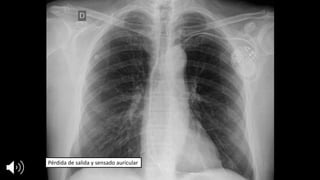

Pérdida	de	salida	y	sensado auricular